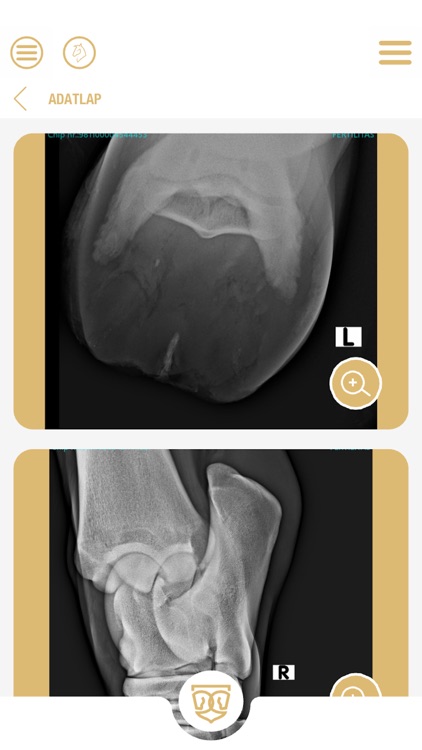

Fontos számunkra, hogy egy megbízható felületet, alkalmazást alakítsunk ki így minden lóról ami nem csikó elérhetőek a röntgen felvételek és az orvosi igazolás is egészségügyi állapotáról.

• Röntgen felvételek